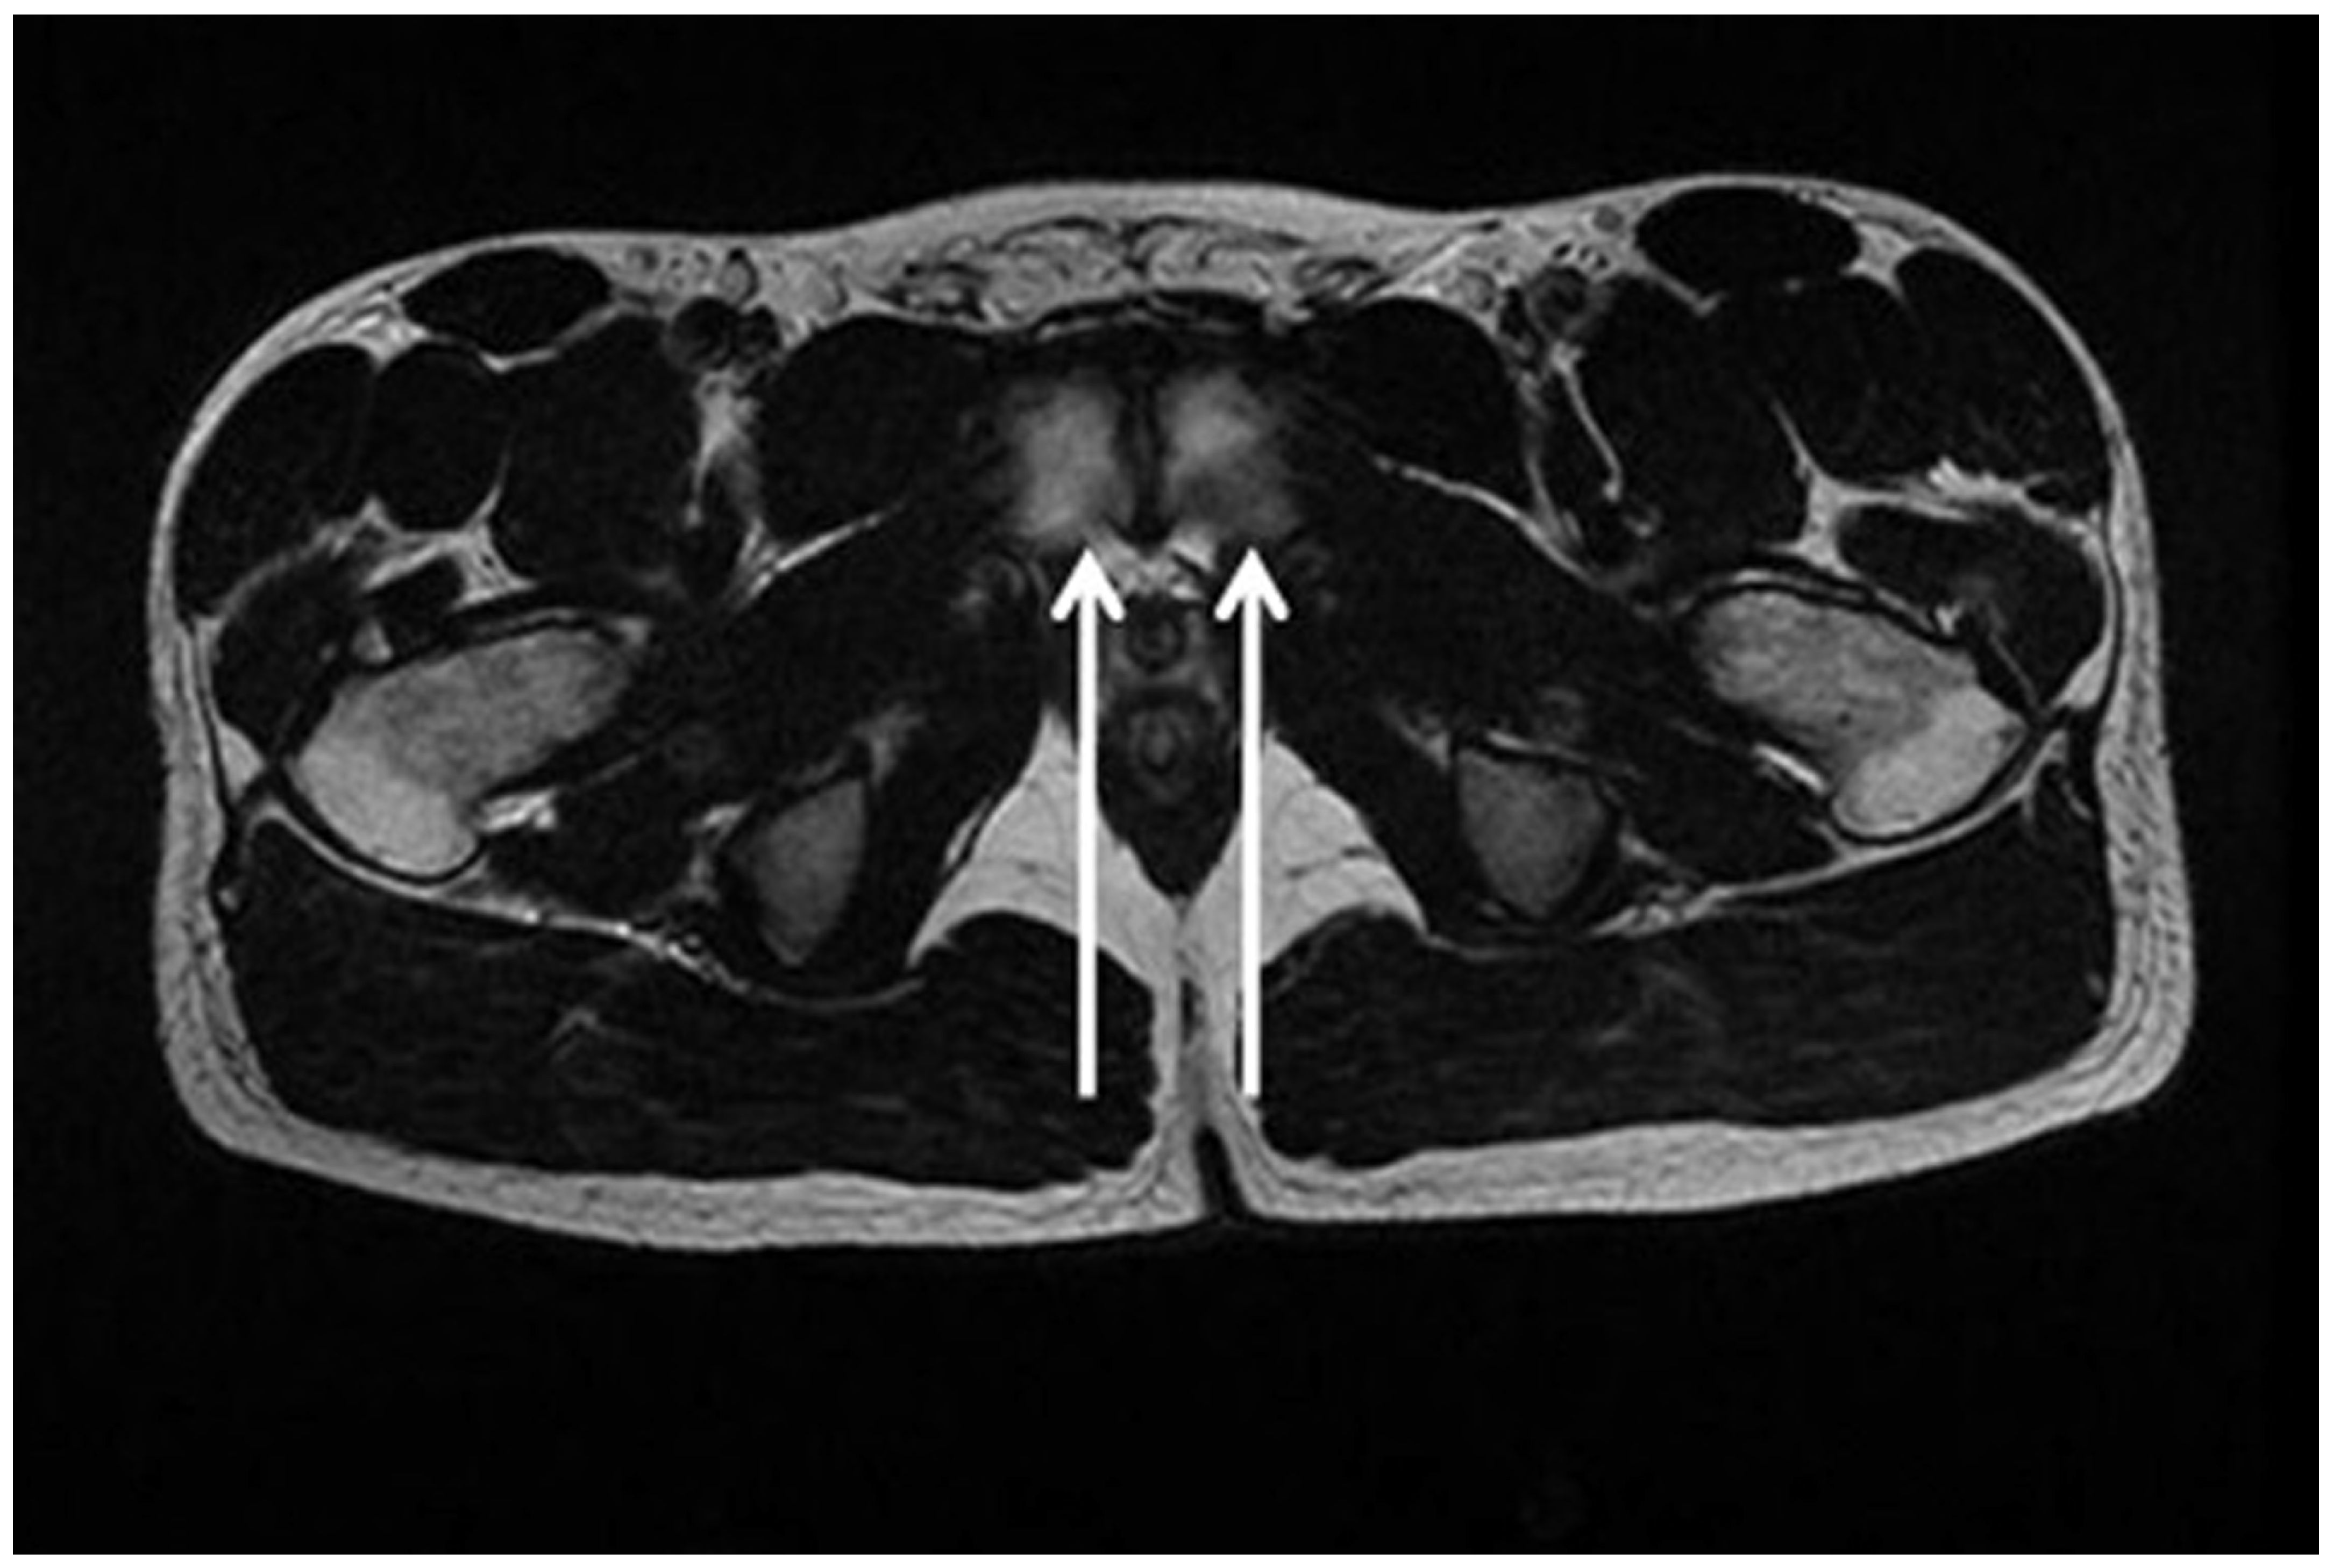

| Bisciotti et al., 2018 [80] | Observational cross-sectional study | IV | 86/90 | lOW | Potential magnetic resonance imaging findings associated with inguinal hernia and inguinal canal posterior wall weakness in athletes |

- Bisciotti, G.N.; Auci, A.; Cena, E.; Corsini, A.; Bisciotti, A.; Zini, R.; Eirale, C.; Parra, F.; Gassaghi, G.; Di Marzo, F.; et al. Potential MRI findings associated with inguinal hernia and inguinal canal posterior wall weakness in athletes. Muscles Ligaments Tendons J. 2018, 8, 290–304. [Google Scholar]